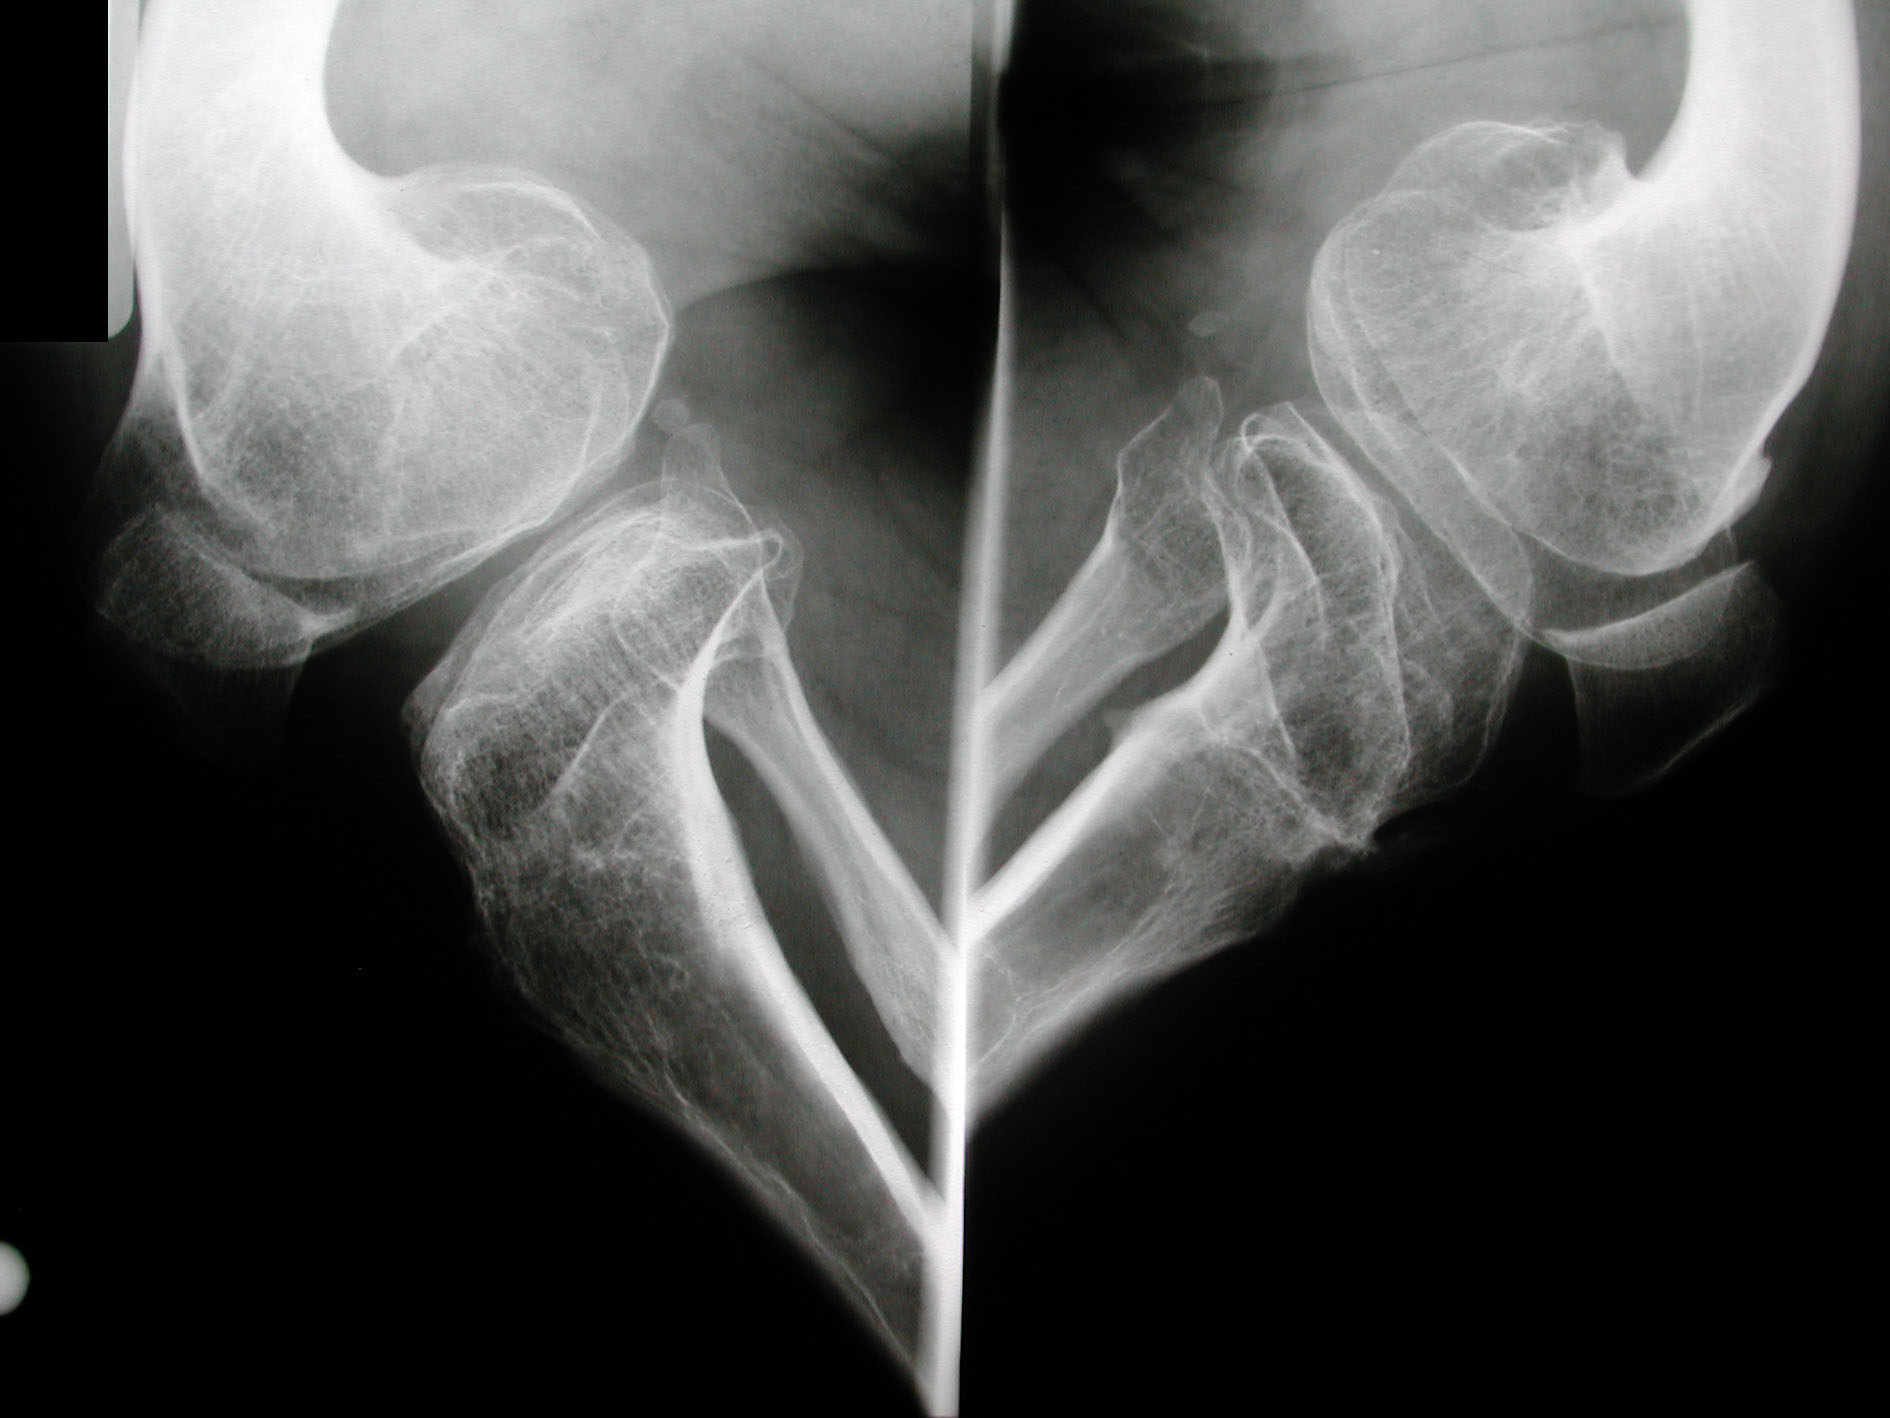

Seudoacondroplasia. [Pseudoachondroplasia]

4. Crossan JF, Wynnes-Davies R, Fulfor GE. Bilateral failure of the capital femoral epiphysis: bilateral Perthes disease,

multiple epiphyseal dysplasia, pseudoachondroplasia, and spondyloepiphyseal dysplasia congenital and tarda. J Pediatric Orthop

1983;3(3):297-301.